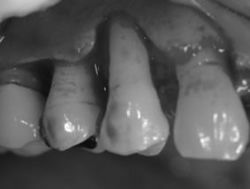

歯周病の症状(歯肉の腫れ、歯がグラグラ、歯肉の出血)を伴って来院されました。見た目(写真左)では、患者さんとしては、それほど悪いようには見えないのですが、診査の結果、重度の歯周病に罹患していることが判明しました。当然のことですが、患者さんは、ご自身の歯の状況を正確には把握していませんので、特に重度の歯周病患者さんの場合、始めてその状況をお伝えする時には、まさか自分かこんな状態なのかと驚き、全く話を信じていただけないことがあります。

治療において一番大事な点は、そういった患者さんの理解を手助けし、十分なコミュニケーションを取りことで、これからどう対処していくのかを患者さんと一緒に考えていくことにあります。十分な相談の結果、歯を保存する再生療法を進めることになりました。 まずは、歯磨き指導から始まる一連の初期治療を終了し、その後、再生療法を行いました。歯肉を剝離して、骨面を露出すると、右上4番の周りの骨が大量になくなっているのがわかります。(写真中央)

歯面を奇麗にした後、再生誘導薬剤を使って、この歯を取り囲み、再生誘導膜を置いた後、歯肉を戻しました。 1年後(写真右)の状態としては、患者さんも定期的に来院され、歯磨きもがんばっていらっしゃるので非常に安定しています。歯肉の腫れ、歯肉からの出血もなく良好に推移しています。